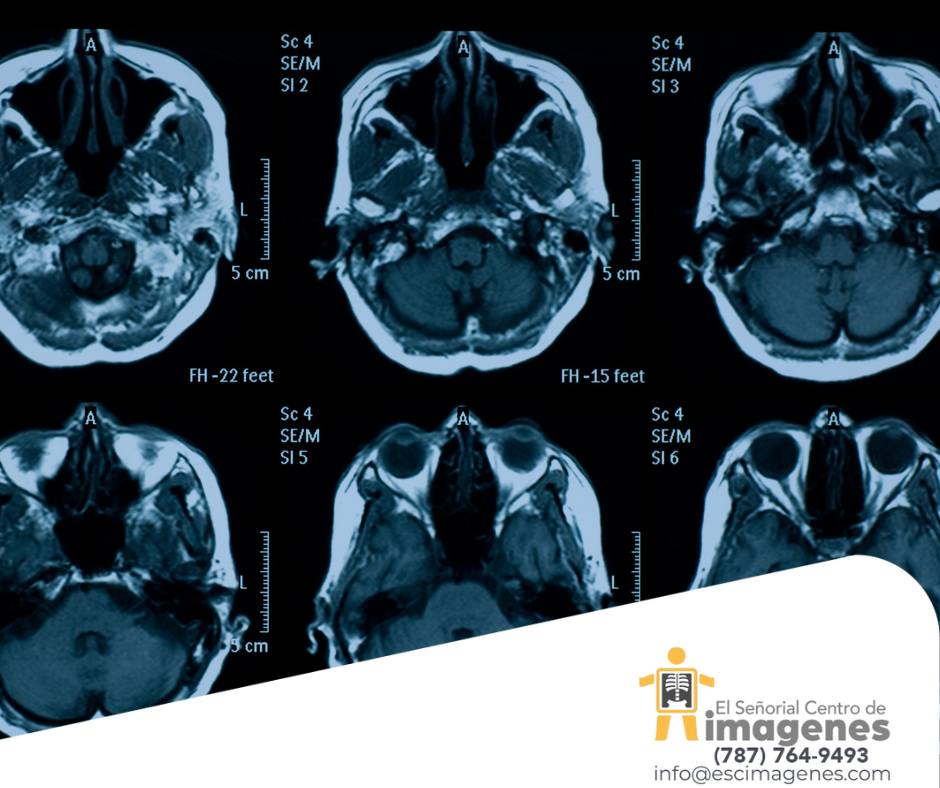

La resonancia magnética puede detectar anomalías cerebrales asociadas con el deterioro cognitivo leve (DCL) y se puede utilizar a su vez para predecir pacientes con deterioro cognitivo leve que podrían, eventualmente, desarrollar la enfermedad de Alzheimer.